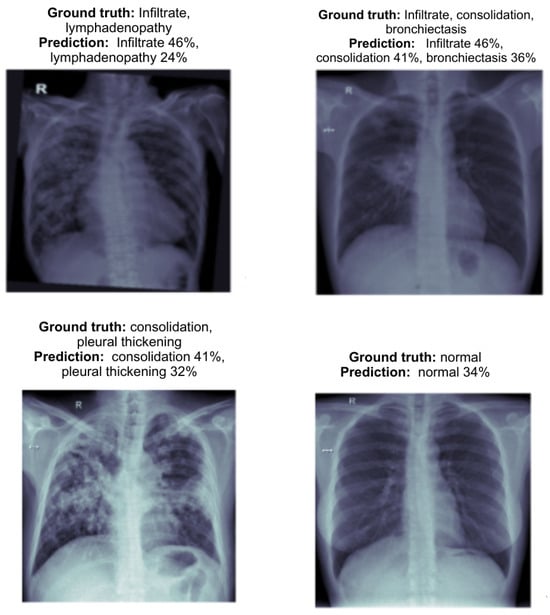

Following the results from this experiment as shown in the Figure 7, the hybrid model showed significant improvements in multi-label classification accuracy. The predictions from the hybrid model demonstrate notable improvements compared to the individual results of the EfficientNetV2L and ViT Base models. The hybrid architecture effectively combines the strengths of both models, particularly in multi-label classification.

First, the hybrid model showed enhanced accuracy in multi-label prediction as shown in the Figure 8. For example, in cases with multiple abnormalities such as infiltrate and lymphadenopathy, the hybrid model balanced the confidence levels between the labels, predicting infiltrate 46% and lymphadenopathy 24%. This represents a significant improvement in consistency compared to EfficientNetV2L, which struggled with lower confidence when predicting multiple labels.

Additionally, the hybrid model provided more balanced predictions for complex cases involving overlapping conditions like infiltrate, consolidation, and bronchiectasis. The model predicted these conditions with greater confidence: infiltrate 46%, consolidation 41%, and bronchiectasis 36%. This shows a better integration of local and global features, addressing the limitations of the individual models.

In terms of detecting pleural thickening and consolidation, the hybrid model performed significantly better than the standalone models. For instance, in one case, it predicted consolidation 41% and pleural thickening 32% with greater accuracy and balance. This improved detection of subtle abnormalities can be attributed to the hybrid model’s ability to extract both fine-grained and high-level features effectively.

Moreover, the hybrid model maintains strong performance on normal cases, predicting normal 34% with balanced confidence. This consistency across both abnormal and normal cases demonstrates the model’s robustness, reducing the likelihood of false positives, which is crucial for clinical accuracy.